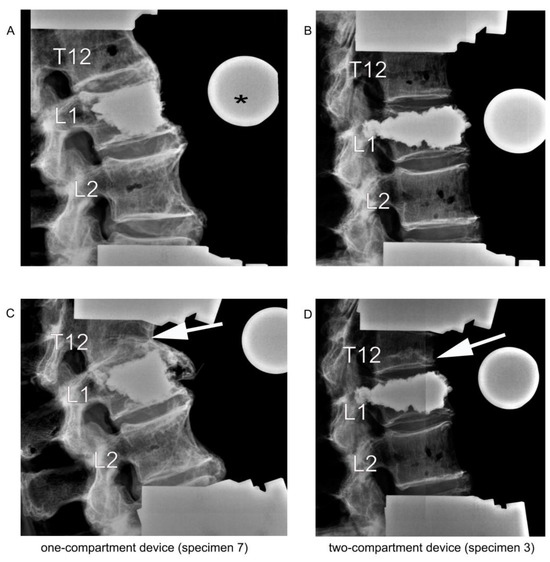

2.5. Radiographic Assessment of Vertebral Height Reconstruction